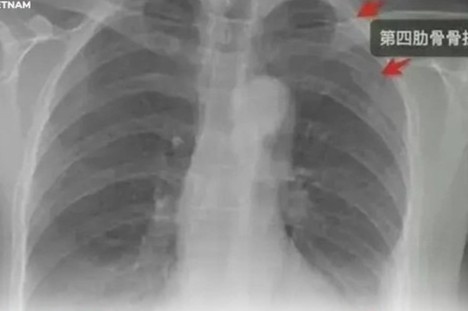

Cô Cao đã khởi kiện đòi bồi thường sau khi bị nam đồng nghiệp ôm chặt đến mức gãy 3 xương sườn.